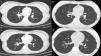

Chest CT. Panels A, C are cuts from pre-procedure scan. Panels B, D are the same cuts from post procedure scan. Calcified right hilar lesion (arrow, panel A). Collapsed RLL segmental bronchi (arrows, panel C). Post procedure, patent RLL bronchus (arrow, panel B). Post procedure, patent RLL segmental bronchi (arrows, panel D).